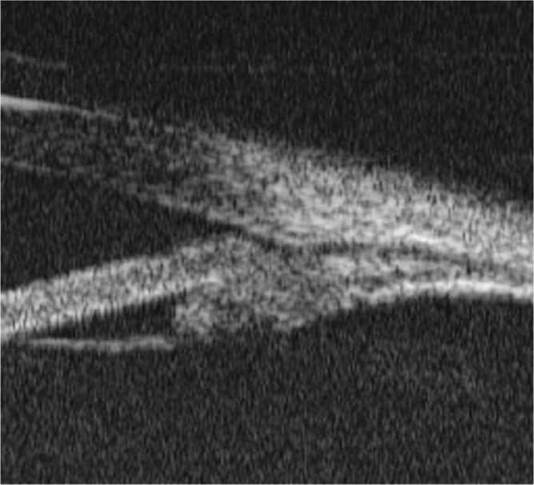

FIGURE 9.1.4 Optical coherence tomography of the optic nerve head (ONH) and retinal nerve fiber layer (RNFL) thickness.

• Baseline documentation of the optic nerves. May include meticulous drawings, stereoscopic disc photos, red-free photographs, and/or computerized image analysis (e.g., optical coherence tomography [OCT] with analysis of the nerve fiber layer and ganglion cell layer or Heidelberg retina tomography [HRT]) (see Figure 9.1.4). Documentation should include presence or absence of pallor and/or disc hemorrhages.